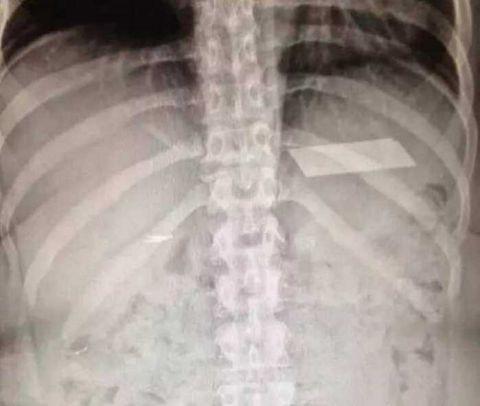

有时候大夫也会留下点什么东西在里面